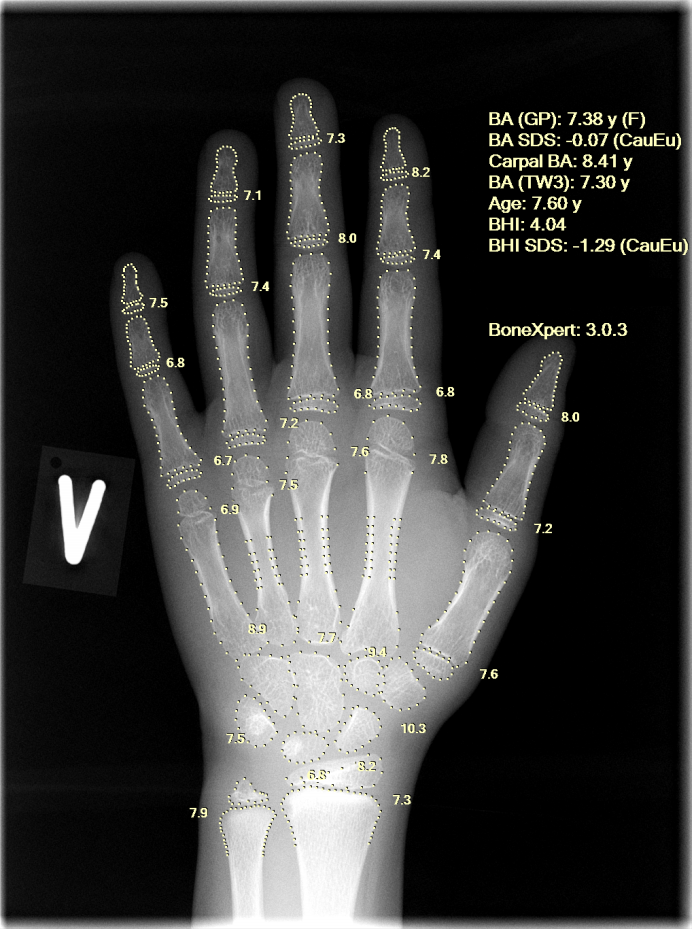

The workflow with BoneXpert Server is illustrated above: After an X-ray is recorded, it is stored in the local PACS. A PACS user (a radiographer or radiologist) can then send the image to BoneXpert for analysis. After 10-30 seconds, BoneXpert returns an annotated X-ray, which is stored in PACS as a new image under the same Study. The PACS user does not directly operate a BoneXpert user interface, what is seen is simply the result: an additional image with the results of the analysis as an overlay; an example is shown here:

The results are instantly available to the radiologist and the requesting clinician via the PACS viewer and can be read off from the image:

| BA (GP): | Greulich-Pyle bone age with decimals (M or F indicates the gender), |

| BA SDS: | Standard deviation score (SDS, also known as Z-score) of GP bone age, based on Healthy Dutch children 1997 BA SDS >0 indicates advanced bone age BA SDS <0 indicates delayed bone age |

| Carpal BA: |

The overall GP bone age of the carpal region |

| BA (TW3): | Tanner-Whitehouse-3 bone age, TW2 can also be shown |

| Age: | Chronological age with decimals |

| BHI: | Bone health index, based on cortical thickness of the metacarpals |

| BHI SDS: | Standard deviation score of BHI |